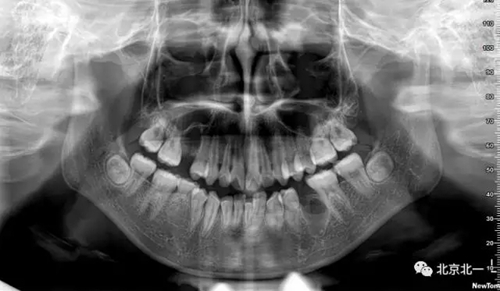

術(shù)后拍片

總結(jié):埋伏牙如果直接硬撬可能會(huì)導(dǎo)致牙槽骨骨折。需要采用微動(dòng)力系統(tǒng)將牙齒有絲分裂后拔除。